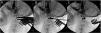

Neurosurgical management of basilar invagination (BI) has traditionally been aimed at direct cervicomedullary decompression through transoral dens resection or suboccipital decompression with supplemental instrumented fixation. Dr. Goel introduced chronic atlantoaxial dislocation (AAD) as the etiology in most cases of BI and described a technique for distracting the C1–C2 joint with interfacet spacers to achieve reduction and anatomic realignment. We present our modification to Goel’s surgical technique, in which we utilize anterior cervical discectomy (ACD) cages as C1–C2 interfacet implants. A young adult male presented to our institution with BI, cervicomedullary compression, occipitalization of C1, and Chiari 1 malformation. There was AAD of C1 over the C2 lateral masses. This reduced some with preoperative traction. He underwent successful C1–C2 interfacet joint reduction and arthrodesis with anterior cervical discectomy (ACD) cages and concomittant occiput to C2 instrumented fusion. BI can be effectively treated through reduction of AAD and by utilizing ACD cages as interfacet spacers.